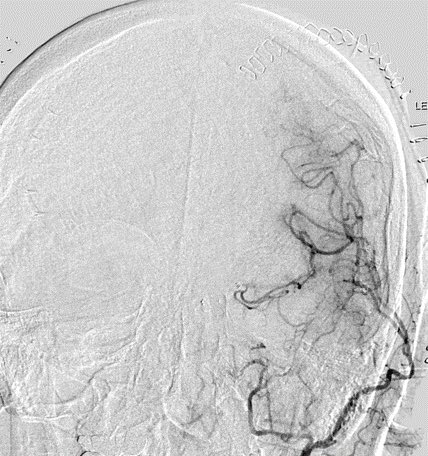

Imaging of Moyamoya disease/syndrome Imaging: Thread-like intracranial ICA/MCA with attenuated branches and “puff of smoke” appearance on DSA Co